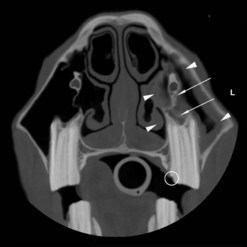

image image image

Fig. 13.36 Polydontia. Supernumerary maxillary cheek teeth (Triadan12s) are the most common supernumerary cheek teeth in horses. The 12 is usually markedly overgrown as in (A) but may be unerupted as in (B) if there is inadequate space (overcrowding). Note the abnormal shape of the apical area of the 112. (C) An example of overgrown bilateral supernumerary mandibular 12s.